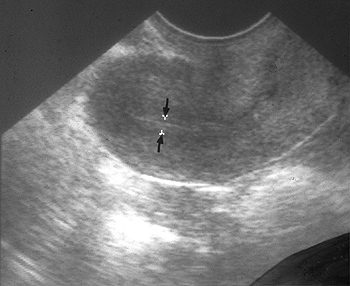

Endometrial (EM) thickness is an importantprognostic factor of fresh embryo transfer and its significance has been proven by many studies. However, only few studies have evaluated the relationship between endometrial thickness and cycle outcome in frozen-thawed embryo transfer (FET). The purpose of this study is to assess the values of EM thickness in hormone replacement(HRT) cycle FET and in natural cycle FET.

We retrospectively reviewed 487 FET cycles using HRT protocol and natural cycle protocol from November 2010 to November 2011. We divided into two groups by EM thickness. Thin EM group was defined by EM < 9 mm and thick EM group was defined by EM ≥ 9mm. We compared cycle outcomes of the two groups in HRT protocol and in natural cycle protocol.

In each group, number of transferred embryos and embryo quality score reflected no difference. In natural cycle protocol, pregnancy rates of thin EM group and thick EM group were similar [31.1%(33/106) vs. 33.3%(52/156), P=0.40]. Ongoing pregnancy rates of thin EM group and thick EM group also were similar [29.2%(31/106) vs. 32.1%(50/156), P=0.12]. In HRT protocol, pregnancy rates of thick EM group were significantly higher than thin EM group [46.3%(50/108) vs. 34.2%(40/117), P=0.04]. Ongoing pregnancy rates of thick EM group were also significantly higher than thin EM group [40.7%(44/108) vs. 29.9%(35/117), P=0.02].

In HRT cycle FET, EM thickness above 9 mm on the day of P supplementation is associated with higher pregnancy rates compared with EM thickness below 9 mm. EM thickness can be used as a predictor of IVF prognosis in HRT cycle FET. However, in natural cycle FET, pregnancy rates did not show significant difference by EM thickness. Therefore, we should pay more attentionto endometrial thickness in HRT cycle FET rather than in natural cycle FET.